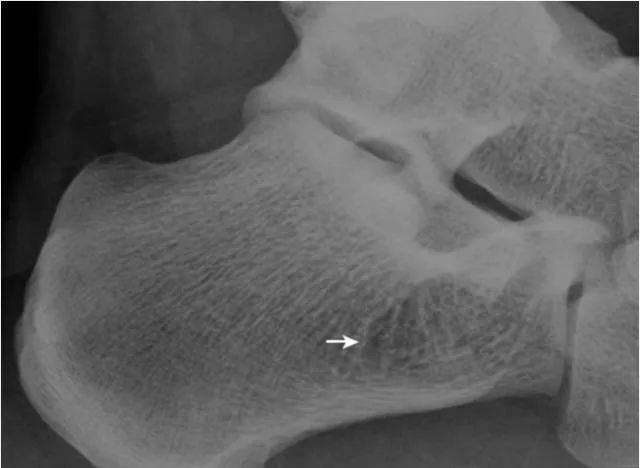

3.跟骨生理透亮区:

正常人跟骨可见三角形的局限性透亮区,为生理性骨小梁稀疏区(箭头),透亮区内骨小梁仍清晰可见。与骨囊肿和脂肪瘤不同,两者因存在骨质破坏,骨小梁显示中断。